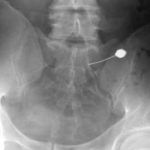

子宮卵管造影

治療

神経根ブロック

シャント拡張術